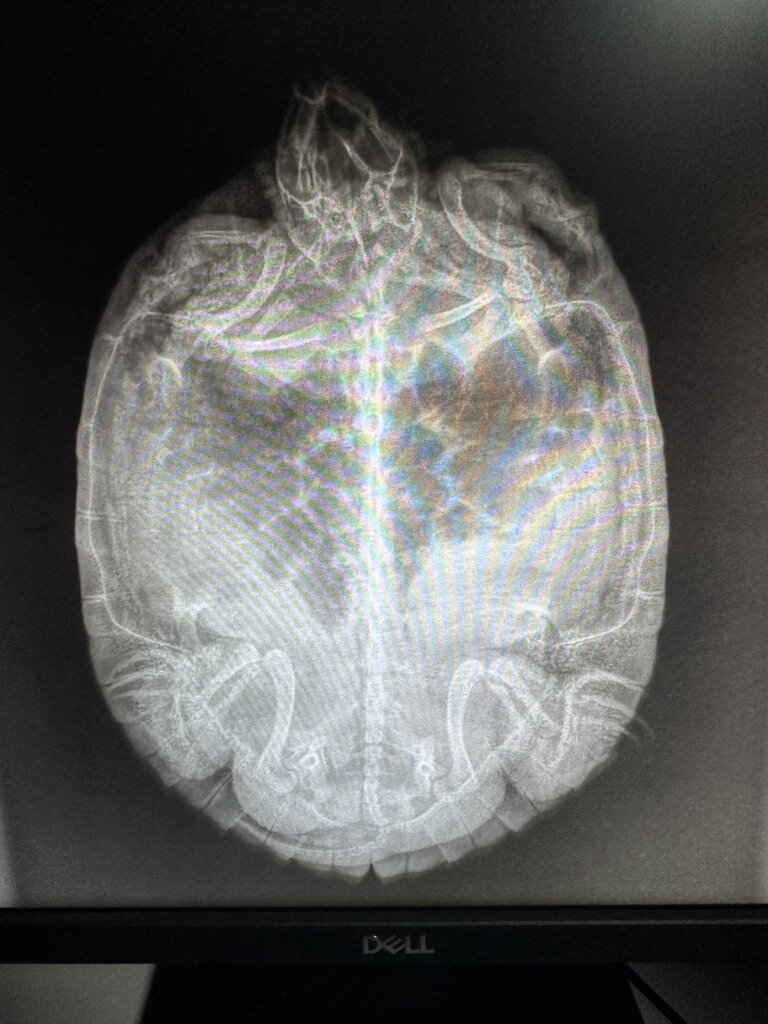

Консультанты moth Ваше имя: Мария Локация: Москва Опубликовано: 8 декабря 2024 Консультанты Опубликовано: 8 декабря 2024 @Alina А. да, нужно лёжа на животе или спине и проекция сбоку/сзади 1

Консультанты moth Ваше имя: Мария Локация: Москва Опубликовано: 8 декабря 2024 Консультанты Опубликовано: 8 декабря 2024 @Alina А. тут скорее всё в куче, рентген покажет у них во время кладки буквально пережимаются все органы, черепаха может около месяца не есть пока не разродится. И движения по жкт тоже не будет.

Alina А. Ваше имя: Алина Локация: Нижегородская область, г. Арзамас Опубликовано: 9 декабря 2024 Автор Опубликовано: 9 декабря 2024 @moth Мария, добрый день! Кое как уговорила в городской вет лечебнице сделать нам узи. Но кажется что там ничего не видно? Там много фото, но здесь не даёт прикреплять больше 5 мг. Может можно Вам лично куда-то отправить фото? На почту, соц.сети

Консультанты moth Ваше имя: Мария Локация: Москва Опубликовано: 9 декабря 2024 Консультанты Опубликовано: 9 декабря 2024 @Alina А. выложите на любой хостинг, а сюда ссылки яиц на снимке нет

Консультанты moth Ваше имя: Мария Локация: Москва Опубликовано: 9 декабря 2024 Консультанты Опубликовано: 9 декабря 2024 @Alina А. по-хорошему Вам бы взять консультацию именно у врача, т.к. на снимках есть мутные области на лёгких и это действительно может быть пневмония https://cherepahi.ru/servisy/konsultatsii/ любой врач из списка если нет возможности - можем начать с лечения авитаминоза и если динамики положительной не будет за неделю - добавить антибиотик